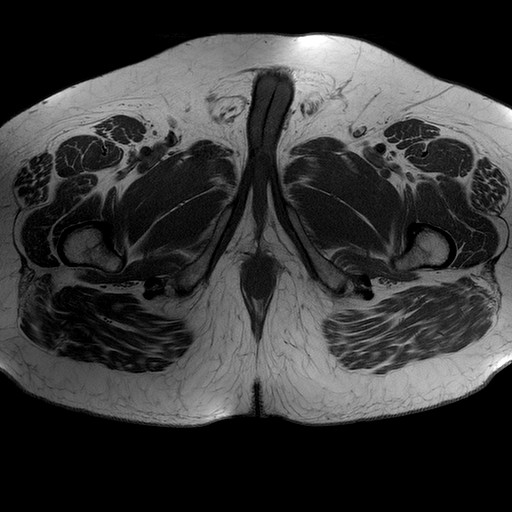

Esami: RMN BACINO

T1W_TSE

Evidenti e simmetriche alterazioni osteofitosiche in regione coxo femorale con riduzione delle rime articolari. Degenerazione completa del cercine glenoideo. Non attuali segni di versamento articolare. Non segni di edema osseo che escludono attuale algodistrofia od osteonecrosi. Lieve e simmetrica riduzione del trofismo della muscolatura glutea.